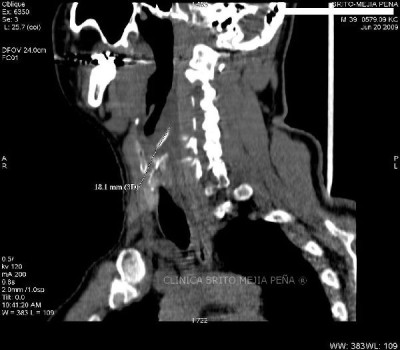

Divertículo traqueal axial

Divertículo traqueal aire